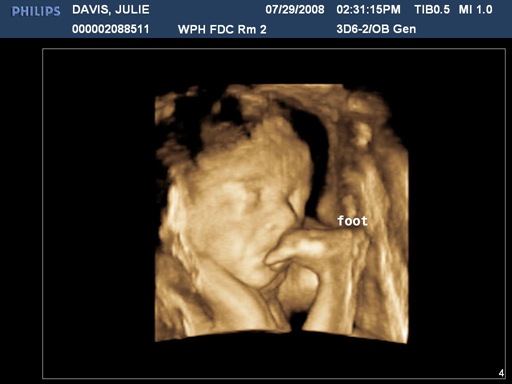

Last week when we went in for the monthly OB checkup, the doctor said that Julie’s belly hadn’t grown as much as expected. Probably nothing, but she wanted to send Julie in for an ultrasound just to make sure. The ultrasound was this afternoon. The ultrasound tech (Megan) was fantastic. Definitely the best experience we have ever had in an ultrasound. I made sure to brag on Megan to her boss.

Towards the end of the ultrasound, Megan switched the machine to 3D. WOW. It was really cool. I hope to get more pictures up in this post later tonight, but in the meantime, check out the picture of my son eating his own foot!